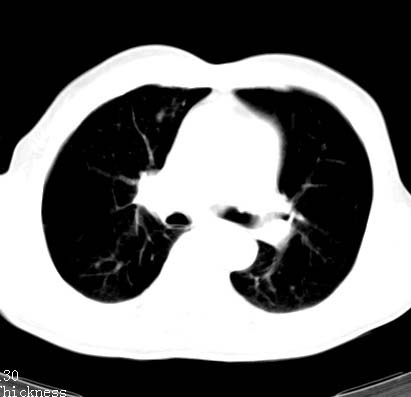

标题: CT14027:男性病人 71岁 咳嗽咳痰数周. [打印本页]

标题: CT14027:男性病人 71岁 咳嗽咳痰数周.

男性病人 71岁 咳嗽咳痰数周.诊断结核应该有保障吧!

结核是要考虑,但肺癌也不能排除.

右上肺结核,请结合痰检除外活动期;右上叶支气管官腔狭窄建议支气管镜或抗僗后随诊除外堵塞性改变。

高度怀疑肺癌,强烈要求纤支镜检查。

支持双上肺继发性肺结核。